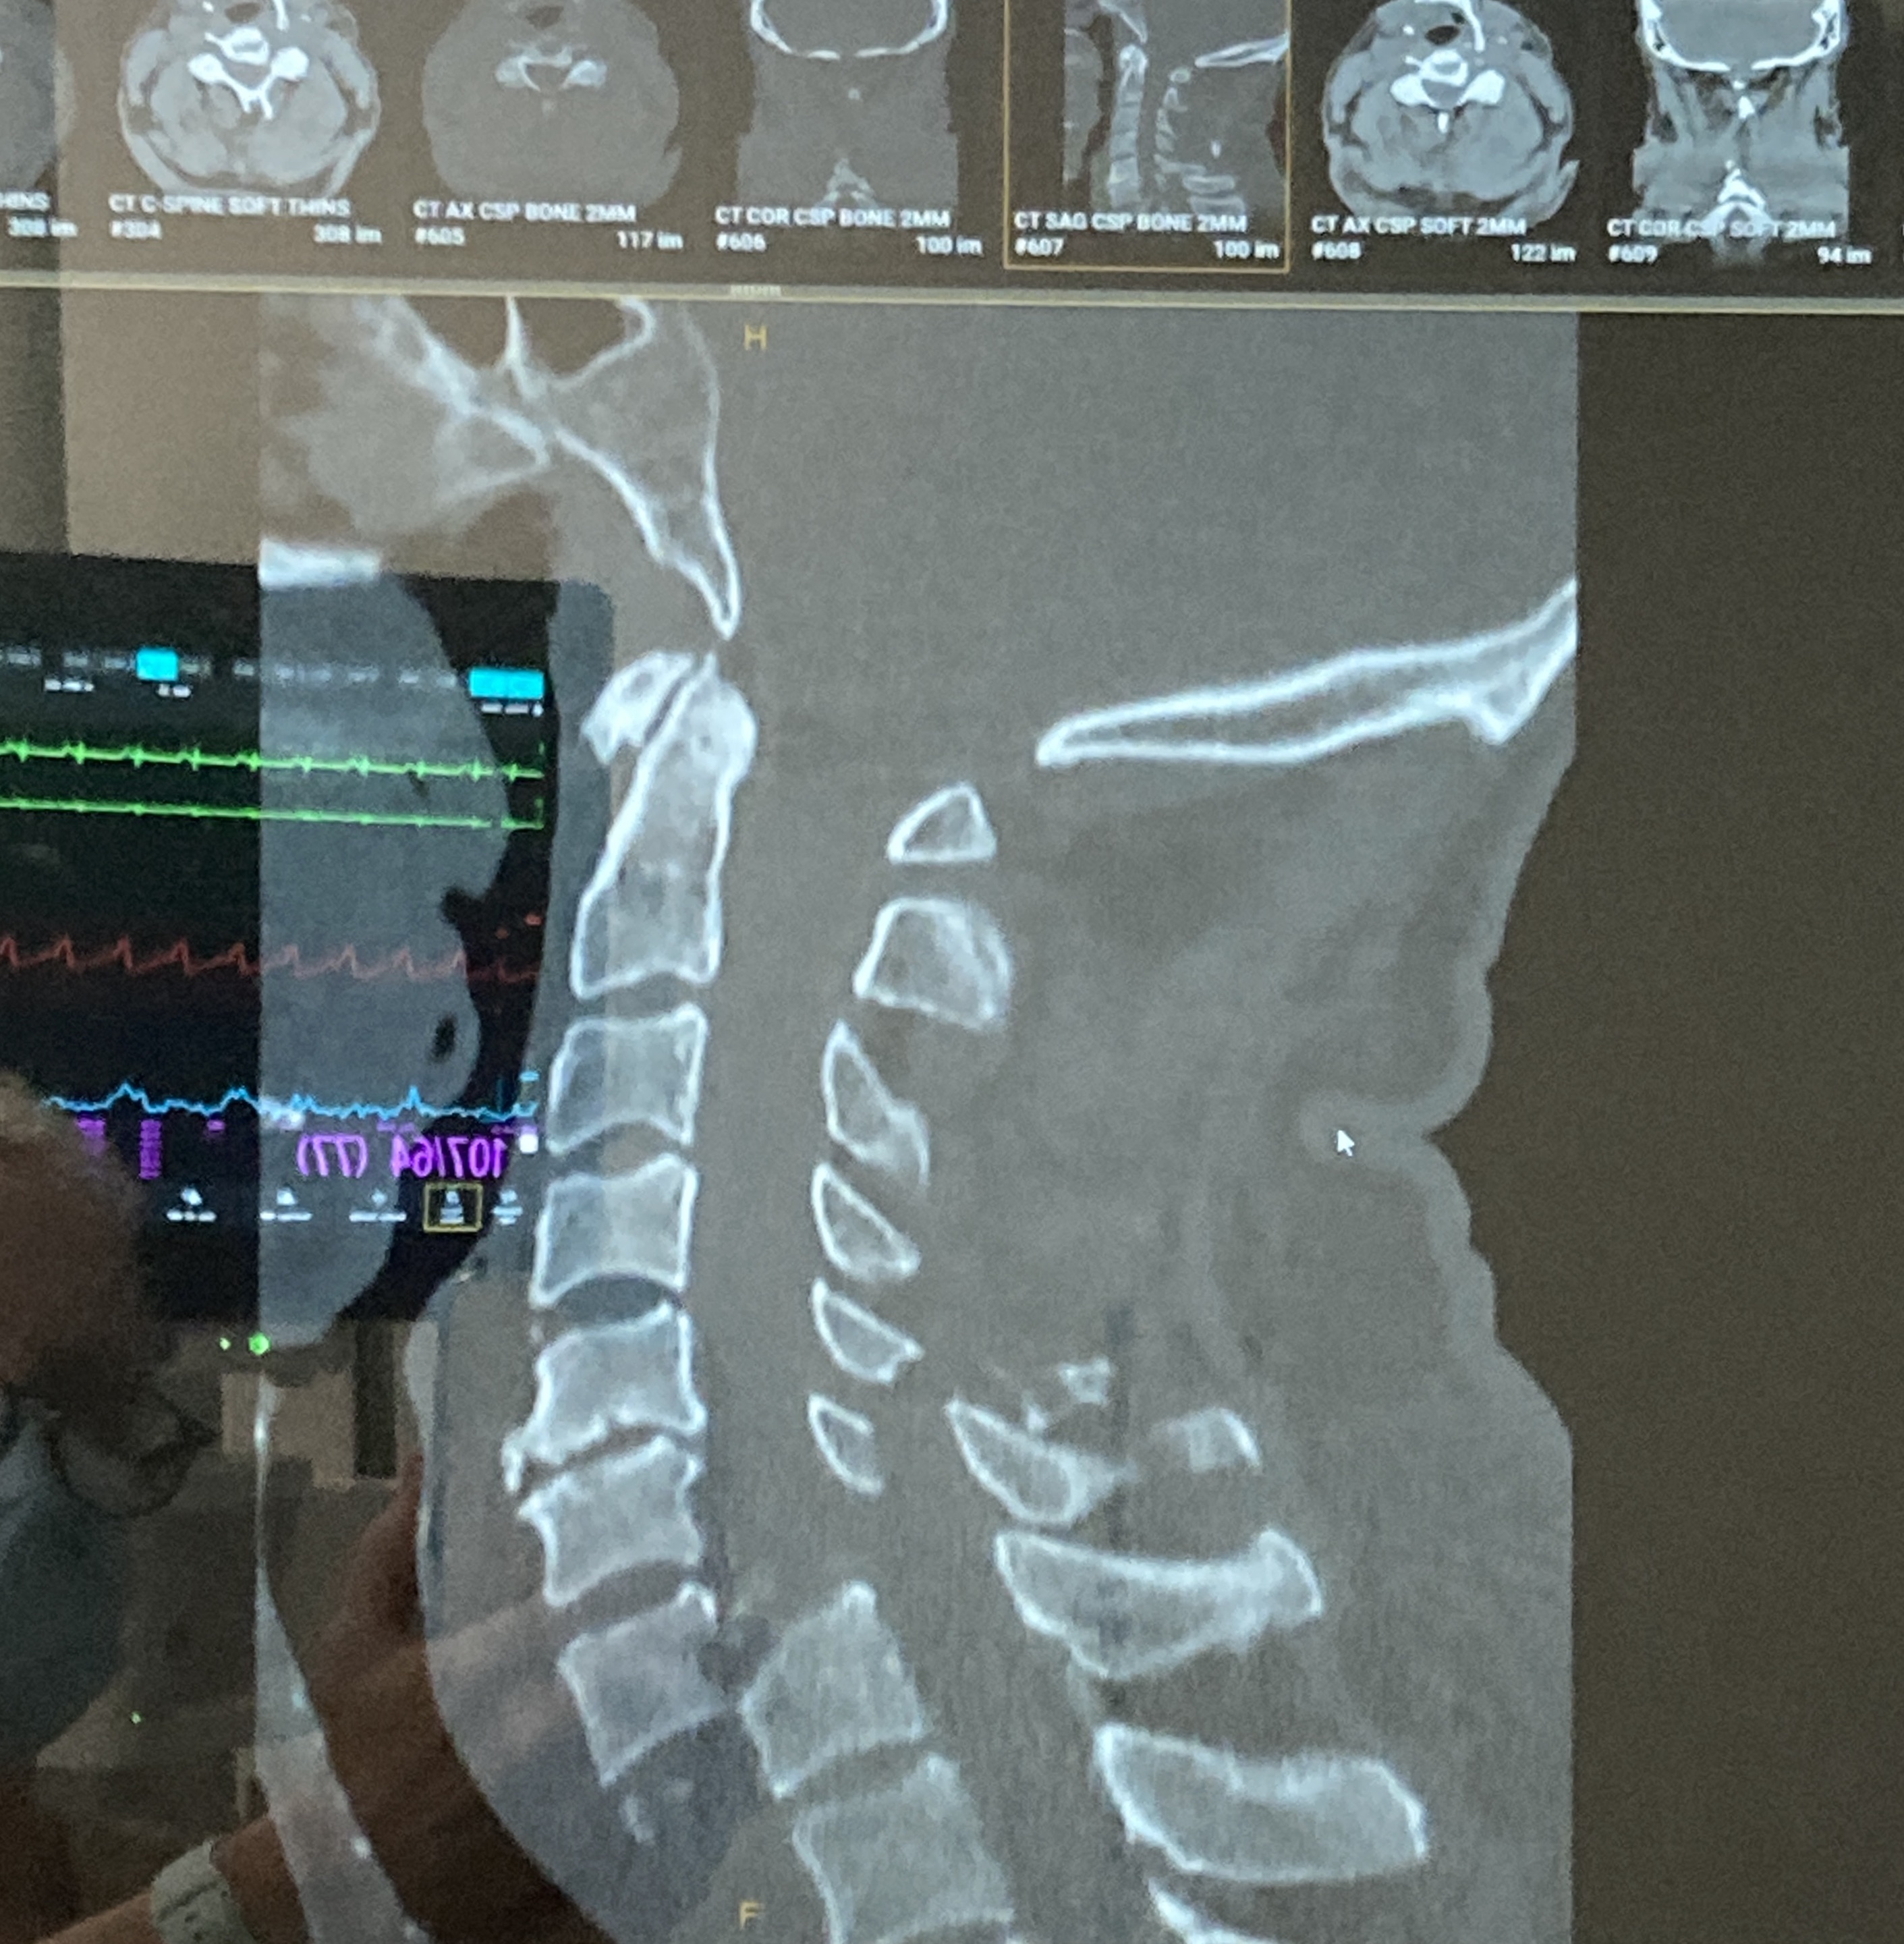

Massive thanks to everyone who has donated to Dean & Becky’s cause so far. For those intrigued by Dean’s condition, you can see the radical neck dislocation in this side-on, pre-op CT scan. The dislocation is between the C6 and C7 vertebrae. His spinal cord is in the black channel between the front and back of the vertebrae. The cord suffered crushing, haemorrhage and swelling across a pretty large area. It’s a really severe injury.